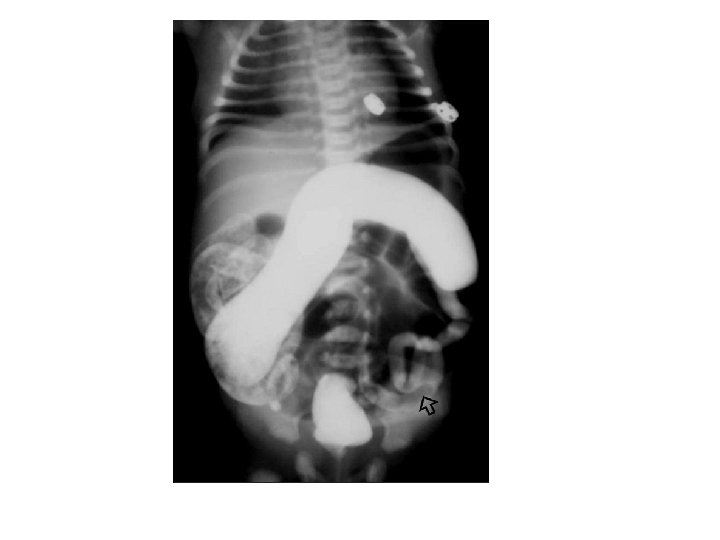

Investigation • Plain film multiple dilated bowel loops • contrast enema 1. small calibre to the left colon 2. multiple filling defects due to retained meconium. 3. transition zone between at the splenic flexure. 4. The enema can be both diagnostic as well as therapeutic & usually accompanied by passage of meconium during the procedure.

Radiological investigation Barium enema Requirement: infant should not have rectal washouts or even digital examinations prior to barium enema, as it may distort the transitional zone appearance and give a false-negative diagnosis.

Radiological investigation Finding Barium enema • stenosed aganglionic segment, • Followed by funnel segment (Transitional zone) • Then dilated bowel.